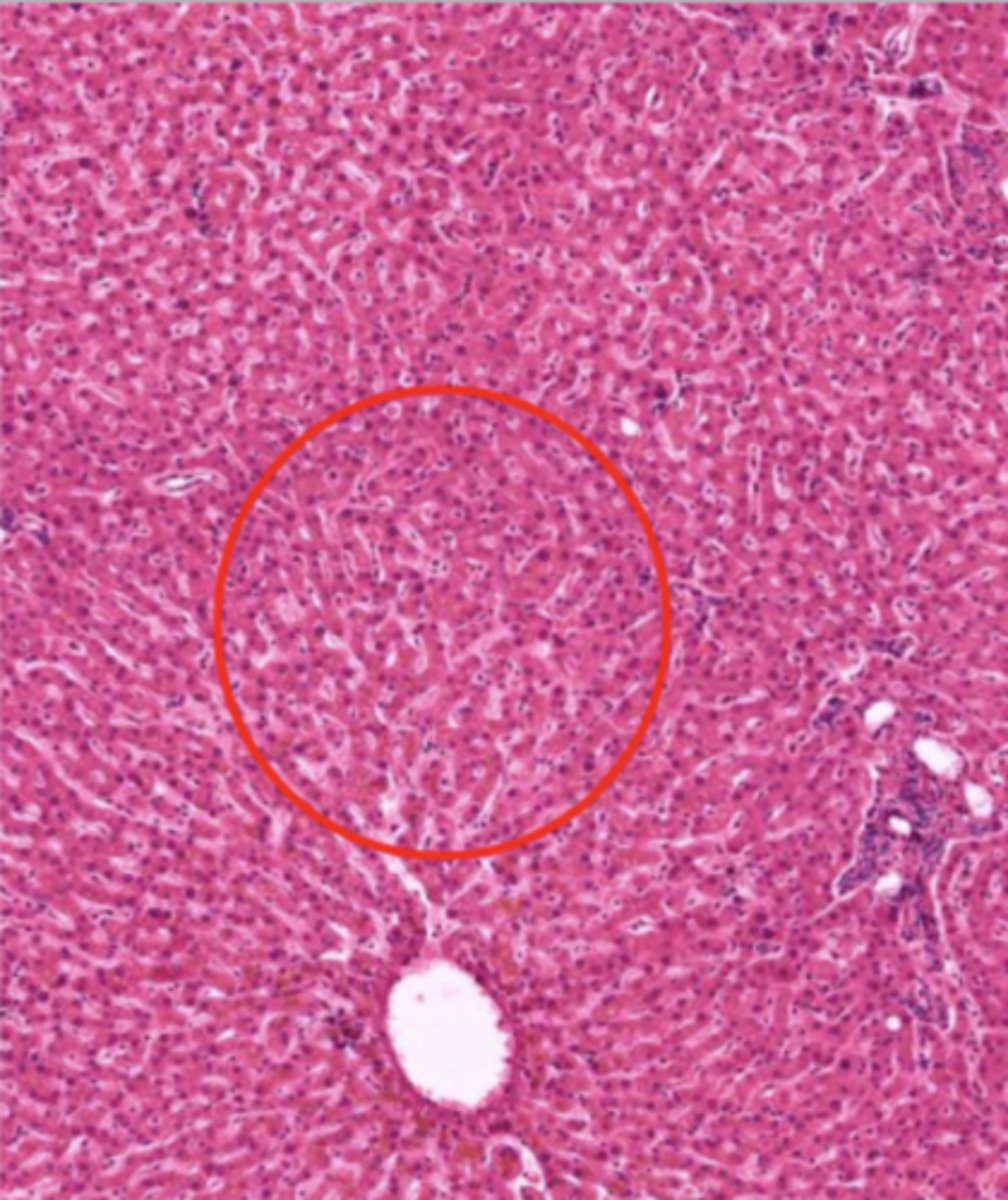

liver (histology)

hepatocyte (liver)